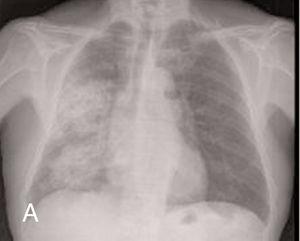

The first relapse of the disease was found two years and 3 months after the ANCA had become positive and while the patient was undergoing immunosuppressive treatment with oral cyclophosphamide at 50mg/day. The patient had anti-MPO at a titre of 367U/ml and the relapse appeared as acute non-oliguric renal failure (creatinine peak at a maximum of 6.6mg/dl), microscopic haematuria and pulmonary haemorrhage in the right lung (Figure 1) that responded to treatment with 500mg pulses of 6-methylprednisone i.v. (three doses) followed by oral prednisone at 1mg/kg/day and 500g pulses of cyclophosphamide. Two months after this first relapse, the patient was admitted to hospital for another respiratory infection without pulmonary consolidation that responded well to levofloxacin.

Figure 1a. Pulmonary haemorrhage in the right hemithorax (A) before treatment and (B) after receiving immunosuppressive treatment.

Figure 1b. Pulmonary haemorrhage in the right hemithorax (A) before treatment and (B) after receiving immunosuppressive treatment.